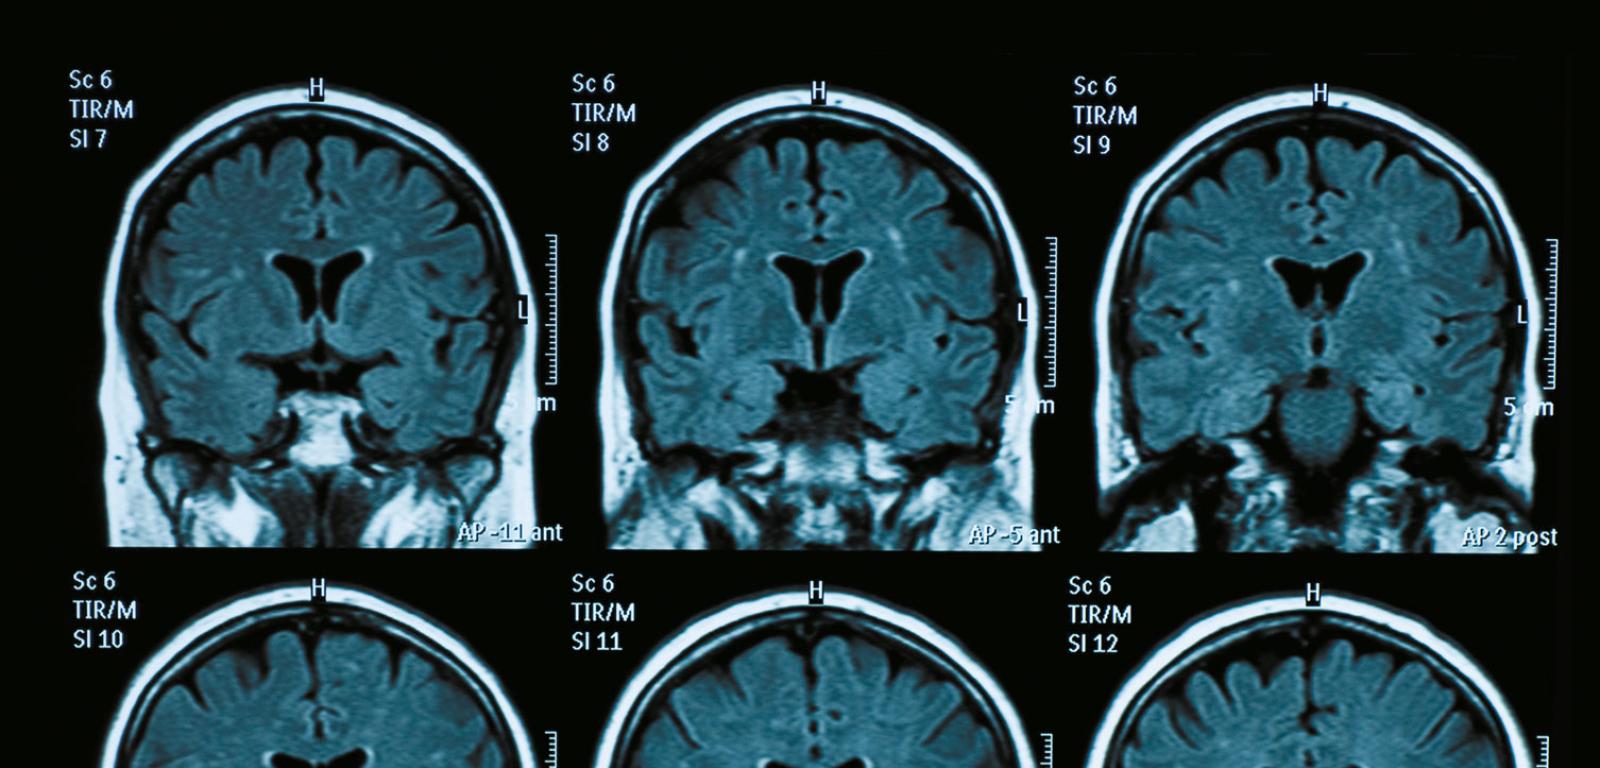

Dwie trzecie ludności świata nie ma dostępu do obrazowania metodą jądrowego rezonan-su magnetycznego. Nadzieją są tanie, małe skanery MRI z ultrasłabym polem.

Obrazowanie metodą jądrowego rezonansu magnetycznego (MRI – Magnetic Resonance Imaging) jest jednym z najważniejszych narzędzi diagnostycznym współczesnej medycyny. Niestety, cena urządzenia waha się od 1 do 3 mln dolarów, a jego instalacja wymaga pomieszczenia dostosowanego do wymogów silnego pola magnetycznego i ekranującego od zewnętrznych źródeł zakłóceń oraz skomplikowanych systemów chłodzących opartych na ciekłym helu. Mniej więcej dwie trzecie ludności świata nie ma dostępu do skanerów, których w 90% znajduje się w najbogatszych krajach.